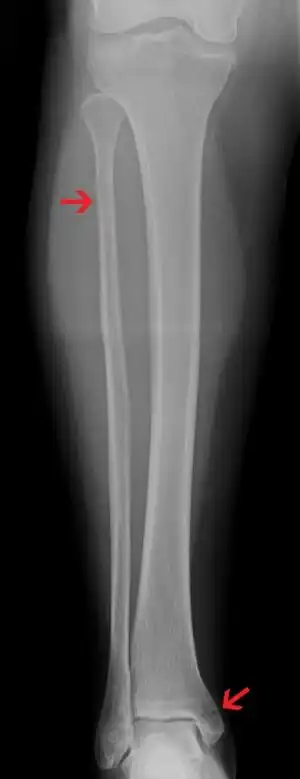

| A Maisonneuve fracture with arrows marking the location of the two fractures | |

It typically results from excessive external rotation of the ankle.[3] X-rays typically show widening of the ankle joint, though this may be subtle.[3][1] Stress views may be useful in unclear cases.[4] People may not mention pain around the knee due to the greater degree of pain in the ankle.[6] It is classified as a type C3 ankle fracture according to the Danis-Weber classification system.[7]

Ankle Xrays are used to detect widening of the tibiofibular syndesmosis or medial clear space. The medial clear space is the area between the talus of the ankle and the medial malleolus. Damage to the deltoid ligament and syndesmotic ligaments result in mortise instability, causing the talus to laterally shift and widen the medial clear space.[9][16] A study found that the medial clear space size of a normal ankle and an injured ankle measured at 4 millimetres and 5.4 millimetres in length respectively.[14] To confirm diagnosis, full-leg radiographs are used to inspect for fractures of the proximal fibula and widening of the interosseous clear space (or tibiofibular clear space). The interosseous clear space is the area between the medial side of the fibula and lateral side of the tibia. A peer-reviewed study, published in Injury in 2004, found that an interosseous clear space greater than 10 millimetres indicates diastasis of the syndesmotic ligaments.[9]